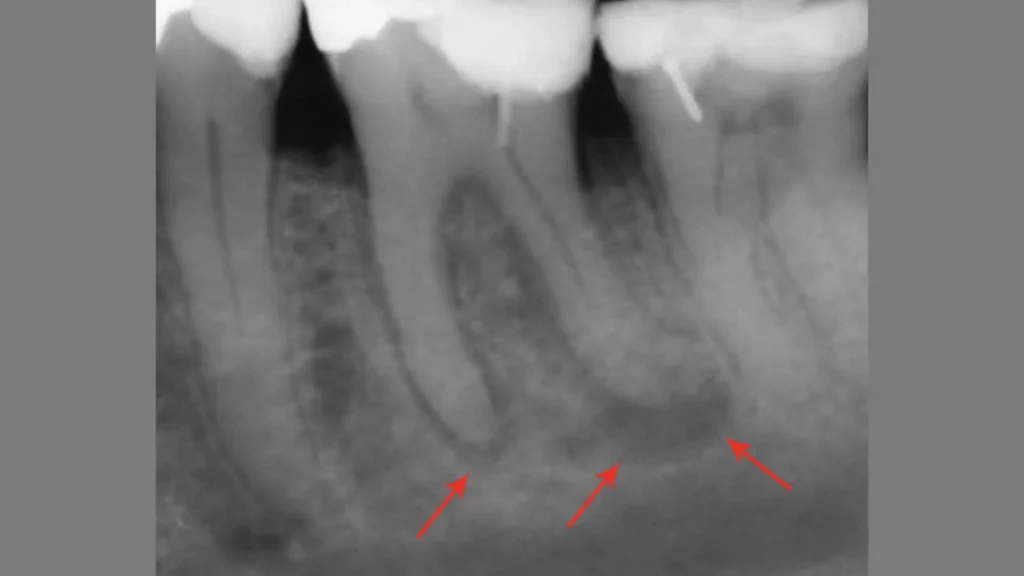

Granuloma Dentale e Danni all’Osso Mandibolare: Un Rischio Silenzioso

Anche se spesso asintomatico, il granuloma dentale non è una lesione da sottovalutare. Quando un’infezione cronica si sviluppa alla radice del dente e non viene trattata, può provocare la progressiva distruzione dell’osso mandibolare circostante. Questo accade perché i batteri e le tossine prodotte dall’infezione stimolano una risposta infiammatoria che intacca i tessuti di supporto del dente, ovvero il parodonto.

Nel tempo, il granuloma può trasformarsi in un ascesso cronico o causare un riassorbimento osseo localizzato, compromettendo la stabilità del dente interessato e, nei casi più avanzati, anche quella dei denti vicini. L’osso mandibolare, pur essendo una struttura robusta, può subire danni permanenti se non si interviene con un trattamento adeguato.